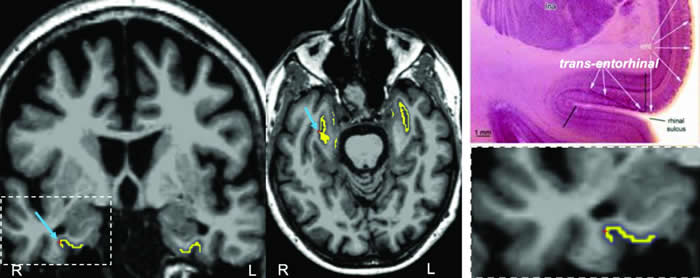

Justin Sanchez和同事设计了一种自动化的解剖采样方法,该方法用PET成像来跟踪脑中TAU的存在。该团队将其技术应用于443名成年参与者(包括55名阿尔茨海默氏症患者)并发现,TAU沉积物首先以独立于β淀粉样蛋白的方式出现于鼻皮层,然后再向颞叶新皮层扩散。对104名受试者所做的一项为期两年的实验显示,那些有着最高初始水平的TAU或β淀粉样蛋白的人会在该研究结束时显示TAU已大多扩散至整个脑部。

作者得出结论:“这些发现提示,[鼻皮层]是下游TAU扩散的一个生物标记…它有可能在治疗试验中有用,因为在这些试验中,TAU扩散的减少是一种转归的检测指标。”